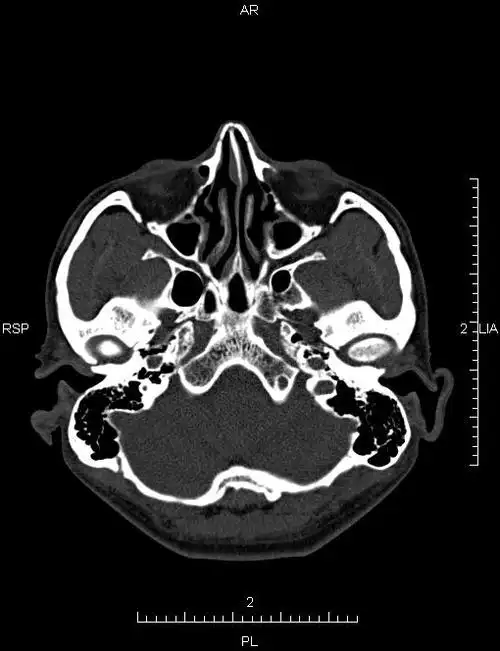

ct51740:鼻骨ct,请会诊!